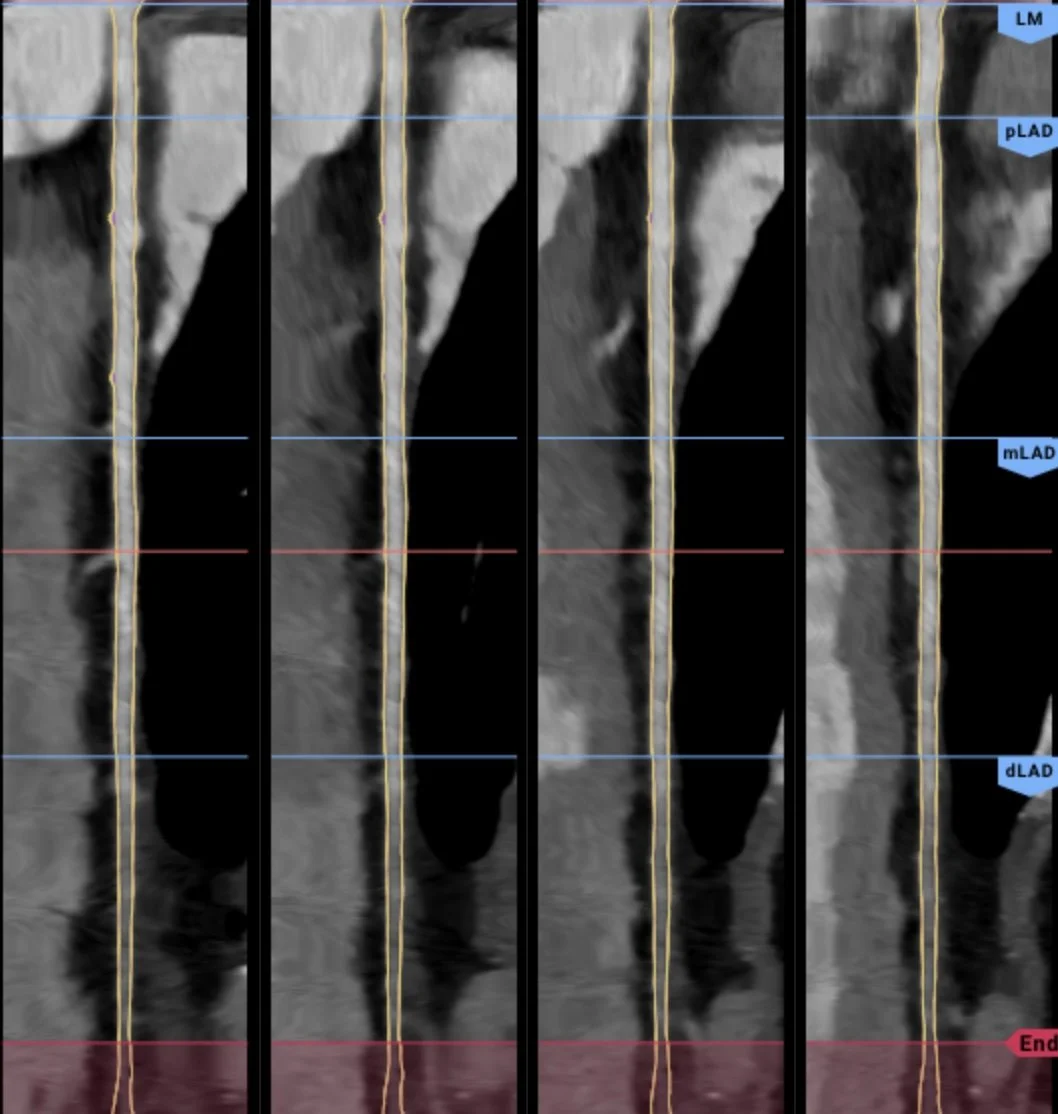

Coronary Computed Tomography Angiography (CCTA) is a noninvasive imaging study that, through the injection of contrast dye via an IV in your arm vein, identifies plaque, narrowing, or blockages in the coronary arteries. This advanced procedure employs a series of X-rays to produce detailed 3D images of your heart and coronary arteries, generating images previously only attainable through invasive heart catheterization.